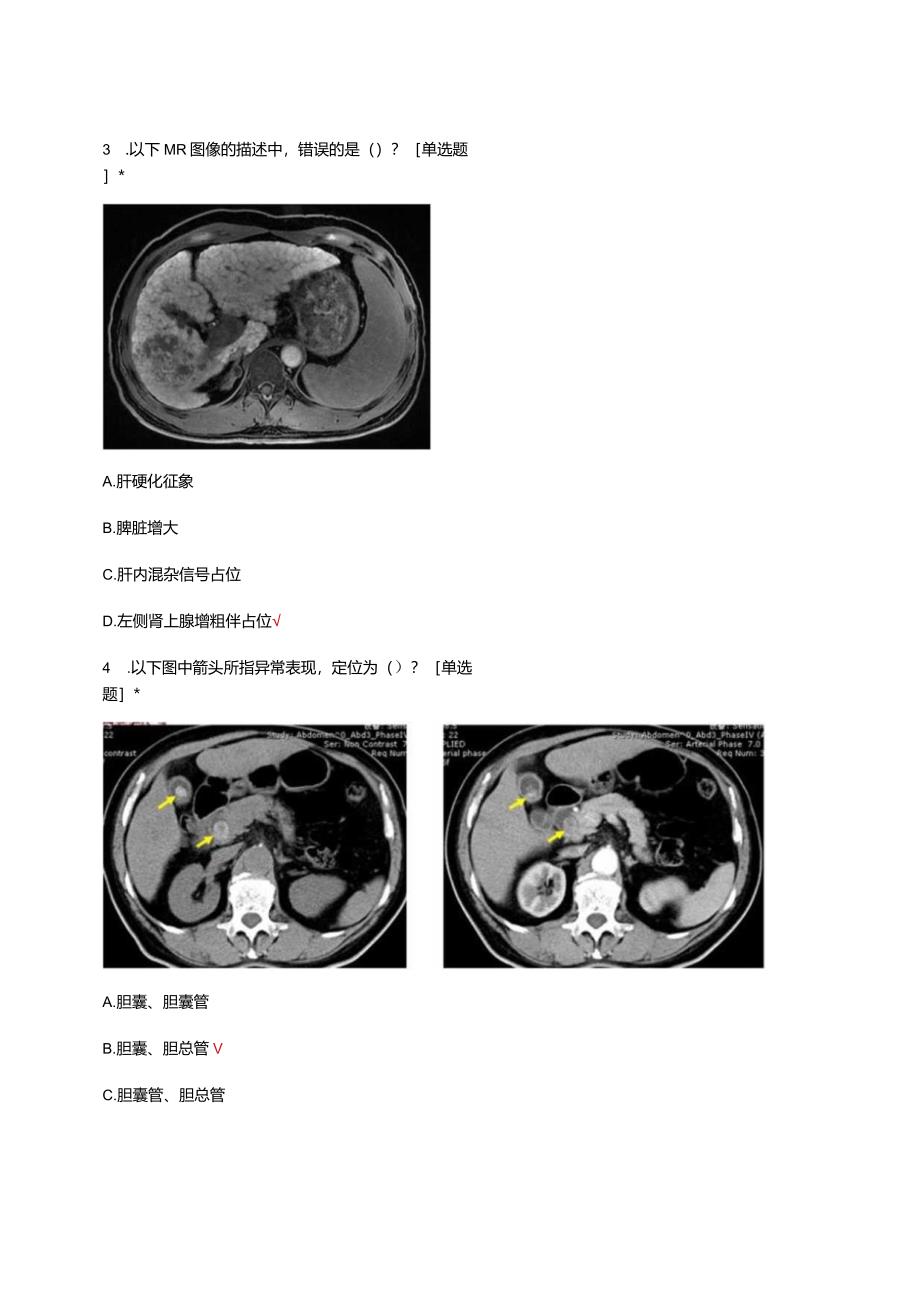

1、放射科临床思维理论考核试题一、选择题1.以下三幅肝脏平扫CT图像,由左到右,肝实质的密度分别是()?单选题*A.正常、正常、减低B.增高、正常、减低C.增高、减低、减低D.正常、减低、2.以下三幅MR图像,由左到右,序列分别是()?单选题*A.T1增强、T2WIxTlWIB.T2WIxTl增强、TlWICTlwI、T2WIsTl增强D.T1WI.Tl增强、T2WI3 .以下MR图像的描述中,错误的是()?单选题*A.肝硬化征象B.脾脏增大C.肝内混杂信号占位D.左侧肾上腺增粗伴占位4 .以下图中箭头所指异常表现,定位为()?单选题*A.胆囊、胆囊管B.胆囊、胆总管VC.胆囊管、胆总管D.胆囊管